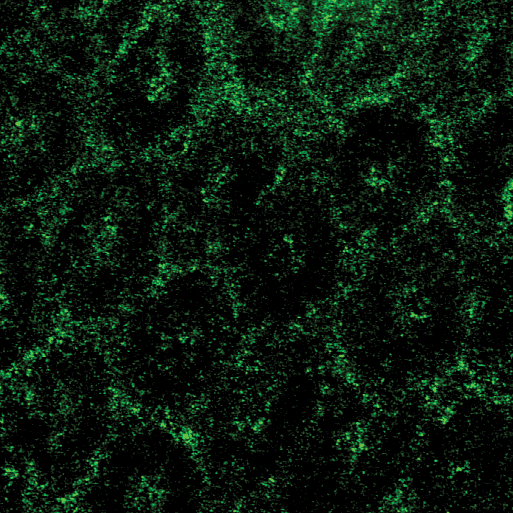

Performing their experiments in mice, the team tested the effects of polymers, which include dietary fiber as well as therapeutics such as medicines for constipation. The researchers fed some mice a diet rich in polymers and others (the controls) a polymer-free diet. Using a technique called confocal reflectance microscopy they measured the thickness of the gut gel and the degree to which the gel was compressed as a result of the consumed polymers. Mice given a high-polymer diet, they found, had a more compressed gel layer.

"The gel is like a sponge with holes that let material through," says the paper's lead author, Sujit Datta, a postdoctoral scholar in the laboratory of Rustem Ismagilov, Ethel Wilson Bowles and Robert Bowles Professor of Chemistry and Chemical Engineering. "We are seeing that polymers, including dietary fiber, can compress the gel, potentially making the holes smaller, and we think that this might offer protective benefits," Datta adds.

In addition, the researchers applied different kinds of polymers—including dietary fibers like pectin, found in apples—directly to the gel lining to test its response. All of the polymers tested compressed the gel layer.

The researchers also found that dietary fiber and gut bacteria—which are part of a community of microorganisms collectively known as gut microbiota—can work together to influence how the gut gel changes shape. They performed the same polymer/fiber experiments in germ-free mice, which are mice carefully raised to not have any bacteria in their gut. The results showed that the polymers compressed the gut gels of these germ-free mice to a greater degree. This implies that species of bacteria in our gut that are known to break down polymers can weaken the compressing effect.